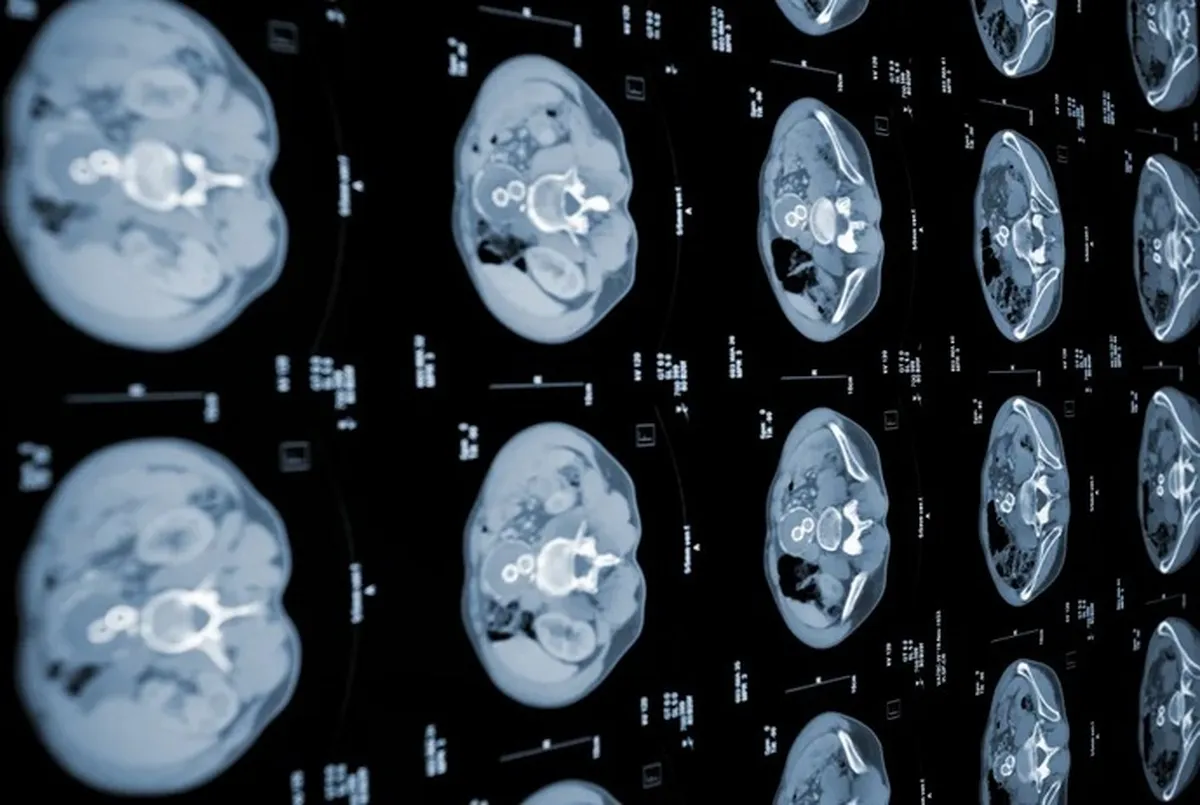

به گزارش خبرگزاری علم و فناوری خبرگزاری آنا به نقل از انگجت، محققان بخش آزمایشگاه علوم کامپیوتر و هوش مصنوعی (CSAIL) دانشگاه «ام آی تی» (MIT) که روی مهندسی کامپیوتر و توسعه هوش مصنوعی تمرکز دارد، دو الگوریتم یادگیری ماشینی ساختهاند که میتوانند سرطان پانکراس را در آستانه بالاتری نسبت به استانداردهای تشخیصی فعلی تشخیص دهند. این دو مدل با هم برای ایجاد شبکه عصبی «پریزم» (PRISM) شکل گرفتند. این روش به طور خاص برای تشخیص آدنوکارسینومای مجرایی لوزالمعده (PDAC)، شایعترین شکل سرطان لوزالمعده، طراحی شده است.

این هوش مصنوعی با تحلیل جمعیت شناسی بیمار، تشخیصهای قبلی، داروهای فعلی و قبلی در برنامههای مراقبتی و نتایج آزمایشگاهی کار میکند. در مجموع، این مدل با تجزیه و تحلیل دادههای پرونده الکترونیک سلامت در کنار مواردی مانند سن بیمار و عوامل خطر مشخص در سبک زندگی او، برای پیش بینی احتمال ابتلا به سرطان کار میکند. با این حال، «پریزم» میتواند تعداد زیادی از بیماران را با سرعت و به وسیله هوش مصنوعی تشخیص دهد. در حال حاضر، این فناوری به آزمایشگاههای «ام آی تی» و بیماران منتخب در ایالات متحده محدود میشود.